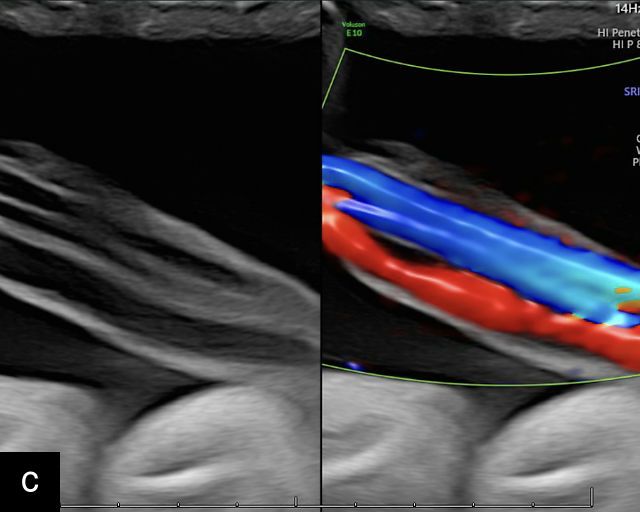

21

(a) Type-1 vasa previa. Photograph after delivery showing the umbilical cord inserting into the membranes through which unprotected fetal vessels run to insert into the placental edge. (b) Type-2 vasa previa. Photograph after delivery showing bilobed placenta with unprotected fetal vessels running though the membranes between the lobes. (c) Type-3 vasa previa in a twin pregnancy. Photograph after delivery showing unprotected vessels running through the membranes from one edge of the placenta to another (arrow). (d) Transabdominal grayscale ultrasound of the lower uterine segment showing a linear hypoechoic structure (fetal vessel) running over the cervix (c) indicating vasa previa (Type 2). b, bladder; h, fetal head. (e) Transabdominal color Doppler ultrasound of the lower uterine segment showing fetal vessels (arrow) running over the cervix (c) indicating vasa previa (Type 2). (f) Transabdominal ultrasound with color flow and pulsed-wave Doppler of the lower uterine segment showing a fetal vessel running over the cervix (c) indicating vasa previa (Type 2). Pulsed-wave Doppler demonstrates an umbilical arterial waveform. (g) Transvaginal grayscale ultrasound with showing a Type-2 vasa previa. There are two placental lobes, an anterior (a) and a posterior (p) lobe. There is a linear and circular hypoechoic structure (arrow) running over the cervix (c) between the lobes. (h) Transvaginal grayscale ultrasound image of vasa previa. A hypoechoic linear structure (arrow) is seen running through the membranes over the cervix (c). h, fetal head. (i) Transvaginal grayscale ultrasound of vasa previa. Hypoechoic circular and linear structures are seen close to the internal os. (j) Transvaginal color Doppler ultrasound image of vasa previa. A fetal vessel is seen running through the membranes over the internal os (arrow) of the cervix (c). h, fetal head. (k) Transvaginal ultrasound with color Doppler showing a Type-2 vasa previa. There are two placental lobes, an anterior and posterior lobe (pl). Fetal vessels run over the cervix between the lobes. (l) Transvaginal color flow ultrasound with pulsed-wave Doppler image of vasa previa. Color Doppler shows flow through the vessel and pulsed-wave Doppler shows a fetal umbilical venous waveform. (m) Transvaginal color ultrasound with pulsed-wave Doppler image of vasa previa. Color flow Doppler shows flow through the vessel and pulsed-wave Doppler shows a fetal umbilical arterial waveform. (n) Transvaginal three-dimensional ultrasound with color Doppler image of vasa previa. h, fetal head; c, cervix.

12

Transvaginal ultrasound imaging of Type-1 vasa previa. Color Doppler (a,c,d) and grayscale (b) imaging shows fetal vessels running over the cervix.